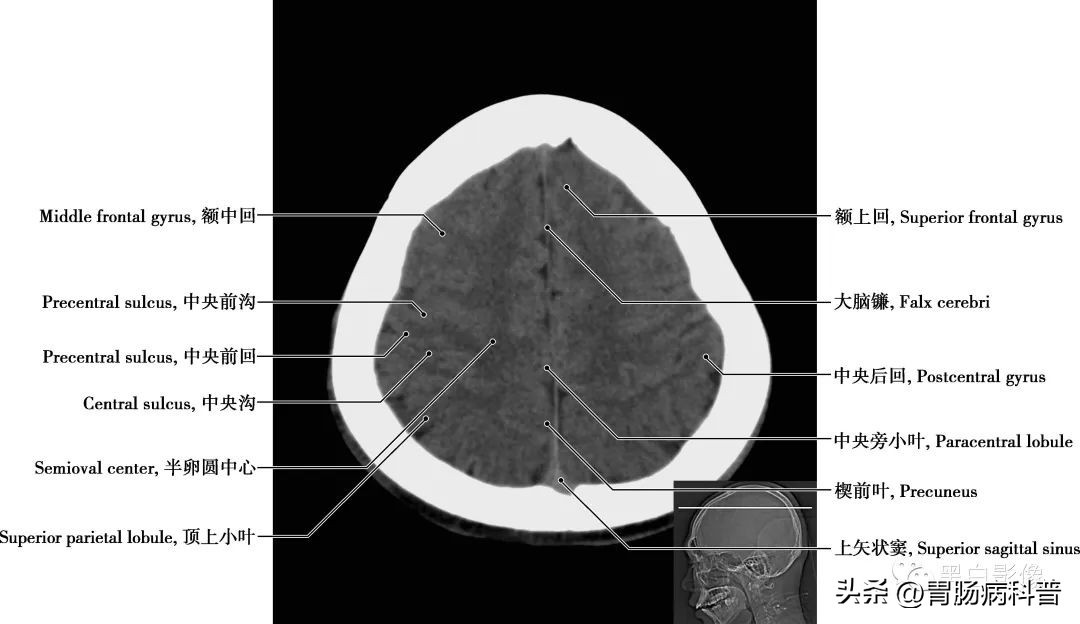

图1-1-4 经中央旁小叶下部轴位切面

中央后回 中央沟和中央后沟之间,是躯体初级躯体感觉区,接受丘脑腹后核的纤维,精确感受对侧半身痛、温、触、压觉以及位置觉和运动觉,也发出纤维组成锥体束,受损时表现为对侧偏身感觉障碍,实体感觉丧失。中央旁小叶 中央前、后回移行至内侧面的部分,前部为初级躯体运动区,后部为初级躯体感觉区